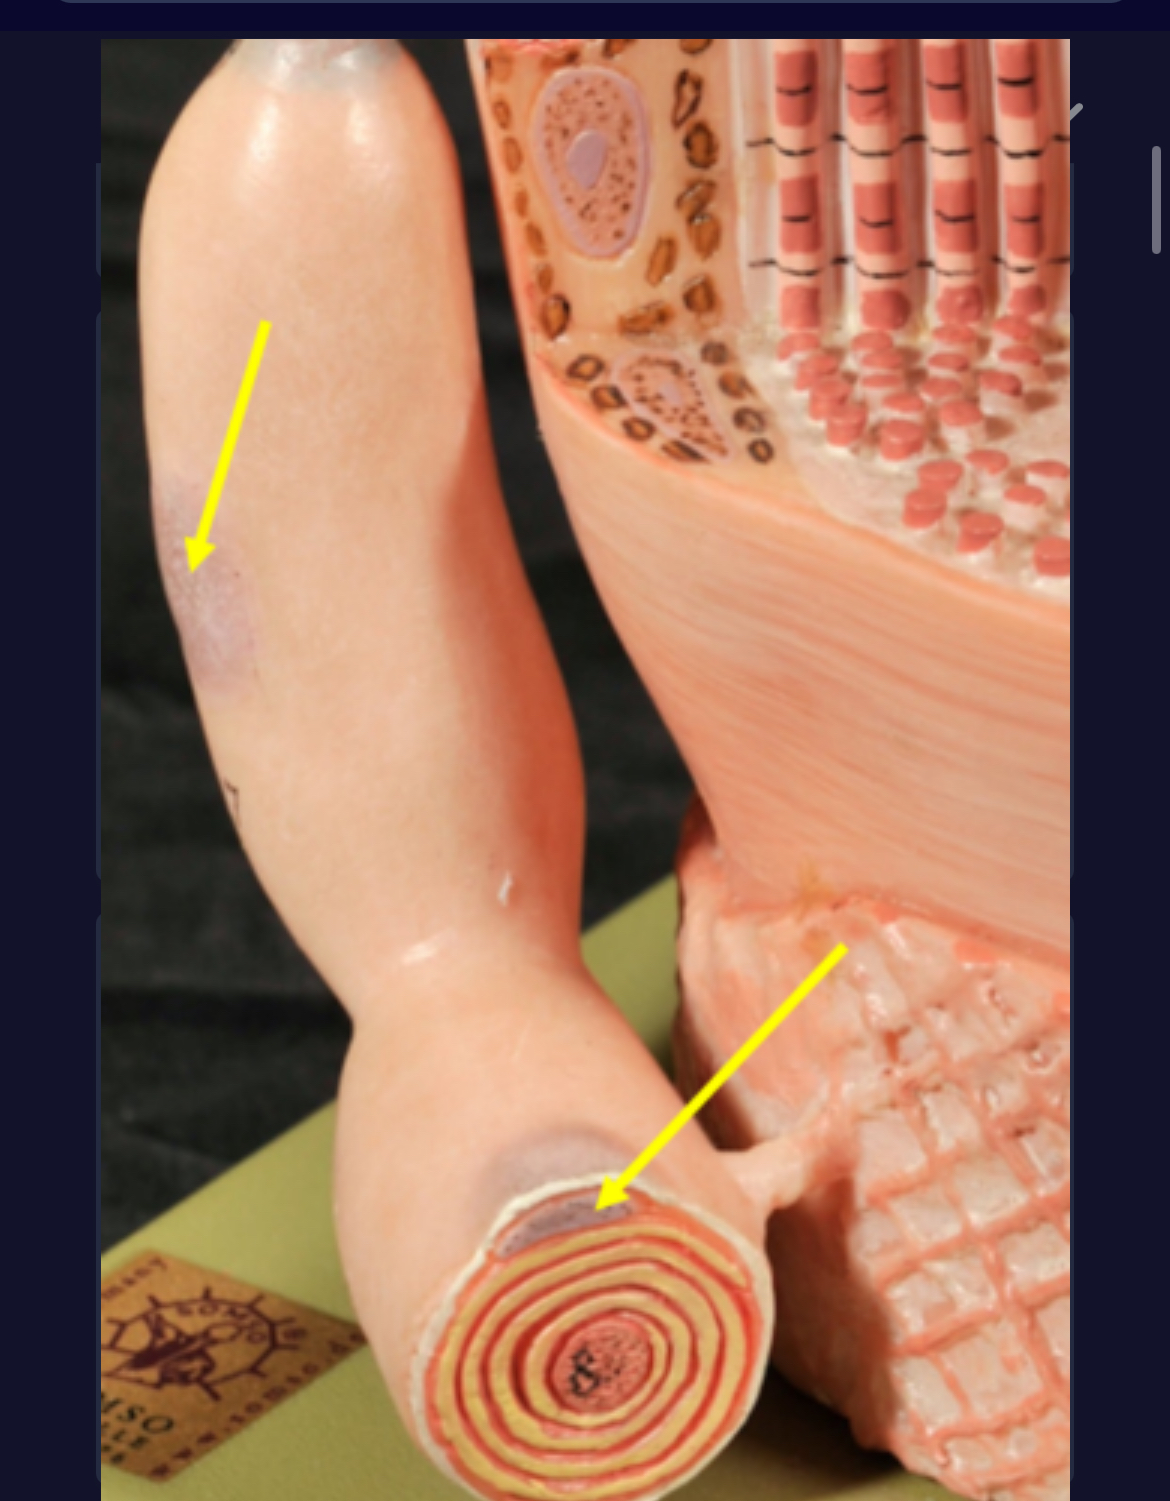

Spinal cord

Cauda equina

Dura mater (outermost layer)

White matter of spinal cord

Gray matter of spinal cord

central canal of spinal cord

Pia matter

Subarachnoid space

Arachnoid matter

Subdural space (brown line)

Dura matter

Epidural space

Dorsal root ganglion

Dorsal root

Ventral root

Spinal nerve